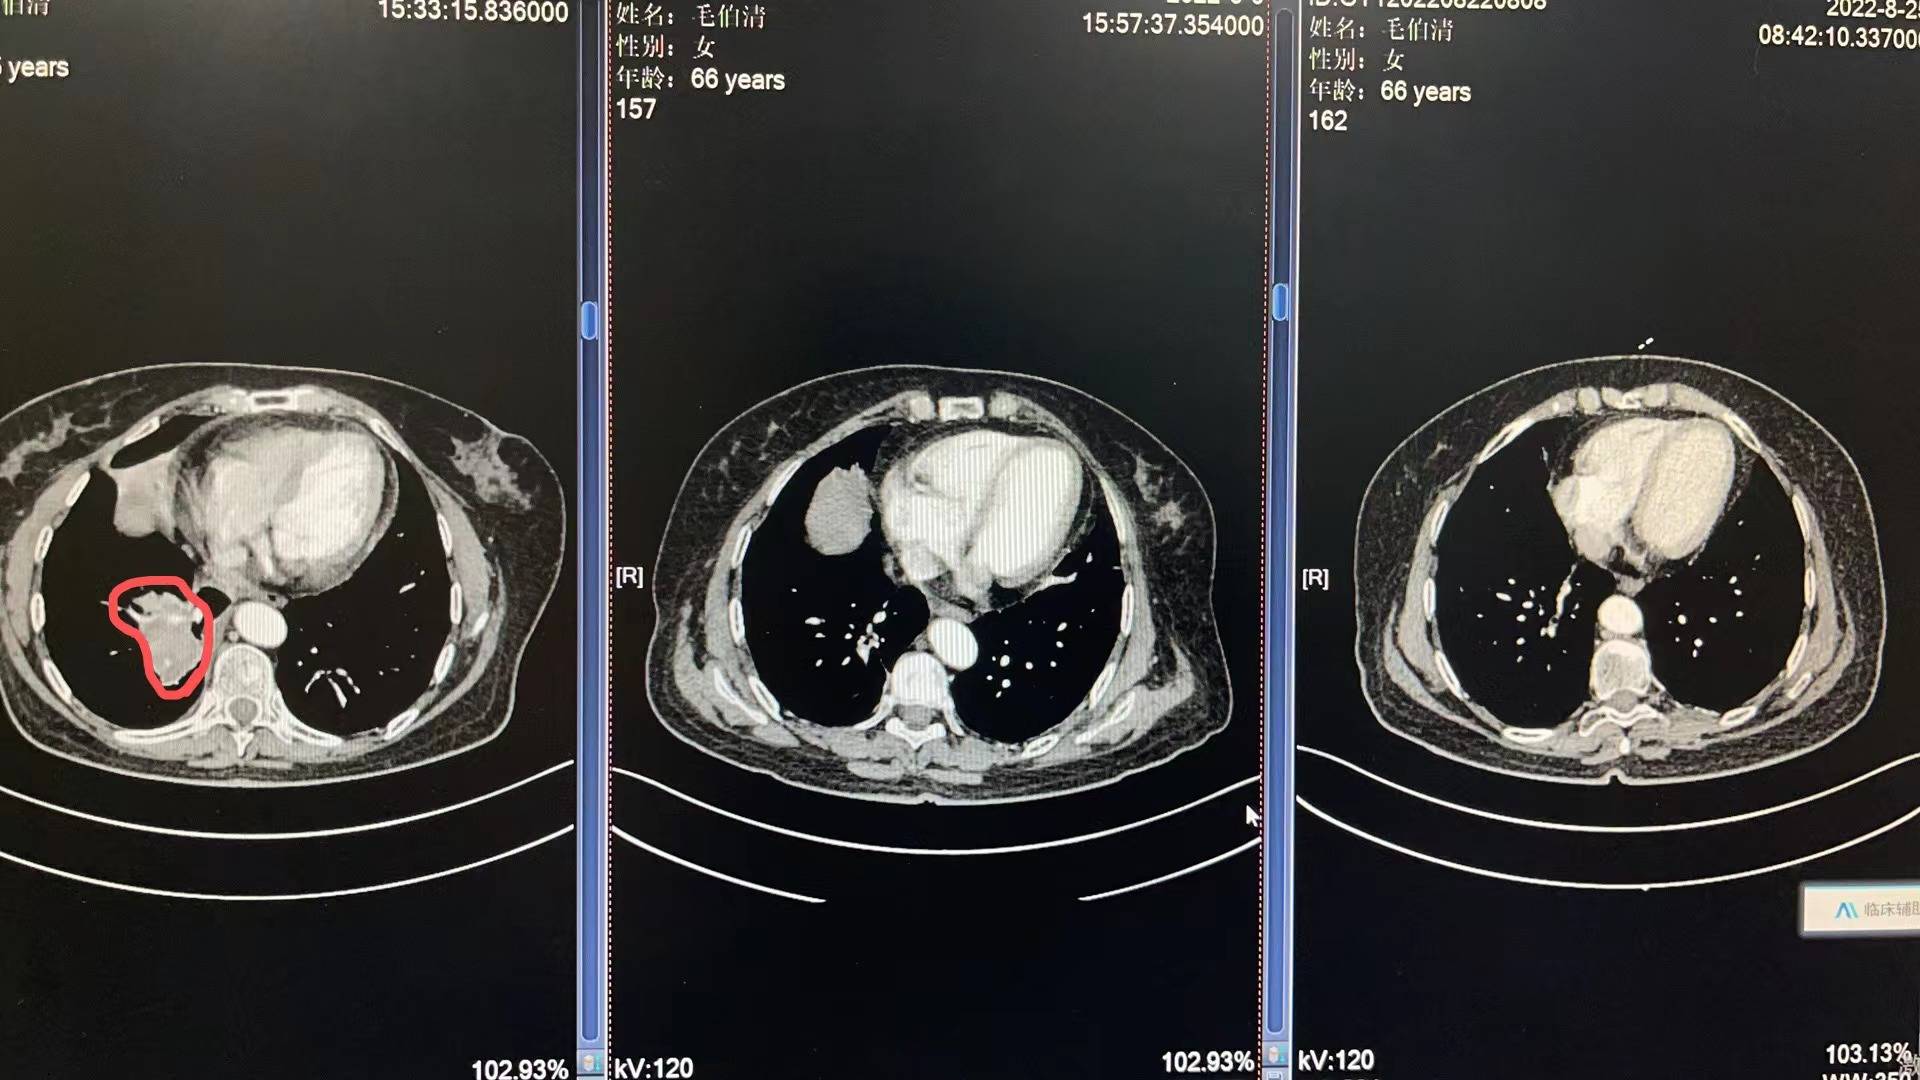

5月3号妈妈入院开始各种检查流程,5月13号病理出来,没有逃过此劫,确诊小细胞肺癌T4N2M0 IIIc期 局限期。妈妈的肿瘤是比较大的,5月14号上治疗,依托铂苷+顺铂,第二次化疗是6月6号,第三次化疗是6月29号,都是化疗三天出院,打升白针,便秘严重,喝乳果糖没啥用,两三天后自然好转。医生开了中药饮片以及一些药出院,刚化疗完那几天妈妈状态很不好,没力气,没精神,喜安静,但是可以下床吃饭,大部分时间躺床上睡觉。食欲不是很好,给她熬的瘦肉粥。四五天后状态开始慢慢好转!7月11号开始放疗,期间停掉第四次化疗,医生说怕身体承受不住,我妈是1天2次,15天完成,20次放疗后出现吞咽有哽咽感,医生只开了一瓶康复新液,就没喝了,7月底放疗结束后,慢慢哽咽感减退,医生让我妈妈回家休息一个把月。

每次她的血常规和肝肾功能都比较不错,有一点贫血的迹象,医生让吃点猪肝和血旺!她的白细胞和血小板都在往下掉,虽然都还在正常值范围内,医生说不错,可是我有一些些紧张!因为妈妈还有三次化疗。前天我妈妈去做了一个胸部复查,她的肿瘤基本没有了,其实在她第二次化疗后复查,肿瘤就小了很多,这次结果医生说还有些残留。准备这次入院化疗给她做一个胸部pet,看看残留的性质是不是活性,如果不是,就表示影像完全没有了。

附上医生给我截图的影像图和复查报告,请比我懂得多,比我专业的朋友帮忙看看!